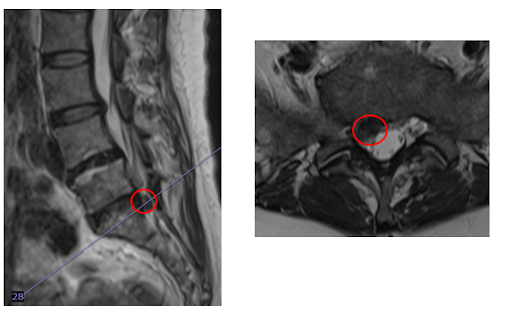

┃検査・診断

MRI検査を行い、赤い枠で示されている部分(L5/S)の椎間板ヘルニアと診断しました。